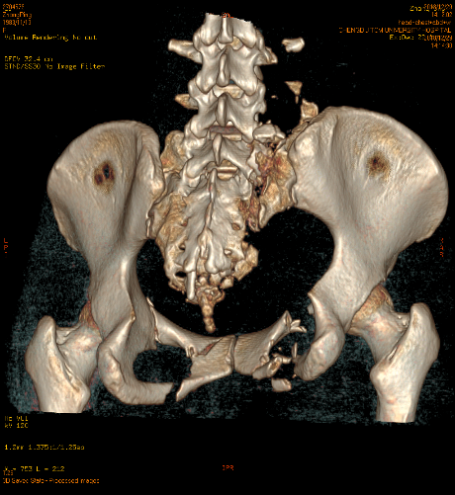

当时,张女士的右肾、胰头及体部均有损伤,还伴有盆腔积液和膀胱内积血。骨盆也有多处骨折:双侧骶翼、右侧耻骨上下支及多个骶、尾椎骨粉碎骨折,骶尾段滑脱;左侧耻骨上下支骨折;胸12椎体及附件;骨折腰1-5椎体右侧横突骨折、断端分离,右侧第6肋骨前段可疑骨折。

患者术前骨盆CT三维重建